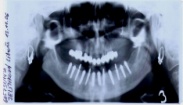

Během let může postupnou ztrátou zubů zůstat v ústech omezený počet zubů, které umožňují držení zubních náhrad.

V důsledku přetížení zbylých zubů např. houpavými pohyb snímacích náhrad dochází k uvolnění těchto zubů a držení můstků a protéz je tak velmi těžké. V těchto případech můžeme pomocí implantátů zvýšit počet pilířů a tím zabránit přetěžování a ztrátě zbylých zubů